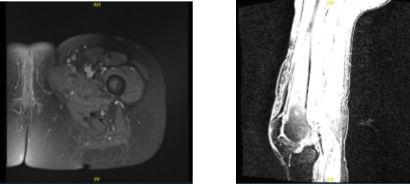

An MRI was reviewed and discussed by the doctor; Left Thigh MRI, the Bones T1 marrow signal intensity is maintained within without evidence for aggressive osseous lesion or osteonecrosis. No acute fracture is present. There is no marrow or periosseous edema.

Please note that this study was not tailored to evaluate for internal derangement of the Joints. Nevertheless, no significant joint effusions are present. There is an oblique tear in the posterior horn of the medial meniscus. The Muscles/Tendons has no full-thickness tendon tear or tenosynovitis is appreciated.

There is no disproportionate muscle atrophy. No acute muscle tear or denervation-related edema is present. There is no peri muscular fluid. The neurovascular structures demonstrate normal course.

The subcutaneous tissues are within normal limits. Oblique tear in the posterior horn of the medial meniscus. No fractures. No muscle tear or muscle edema in the thigh.

MRI Left thigh non-contrast